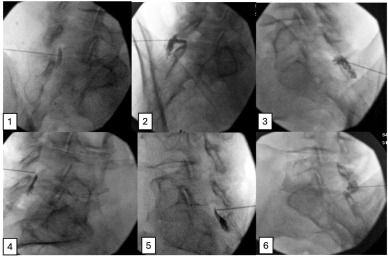

Researchers compared image interpretation using AP versus contralateral oblique (CLO) views. They created a mix of true epidurograms and deliberate non-epidural contrast patterns, then asked ten experienced pain physicians to classify them in a blinded format.

The AP view simply lacks depth information; extradural patterns can easily mimic epidural spread when viewed straight-on. CLO, by contrast, clearly shows the interlaminar window, needle depth, and characteristic epidural flow patterns—even with small contrast volumes.